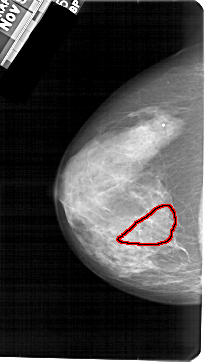

A_1605_1.LEFT_CC

LEFT_CC LINES 5416 PIXELS_PER_LINE 3061 BITS_PER_PIXEL 12 RESOLUTION 43.5 OVERLAY

FILE: A_1605_1.LEFT_CC.OVERLAY

TOTAL_ABNORMALITIES 1

ABNORMALITY 1

LESION_TYPE CALCIFICATION TYPE PLEOMORPHIC DISTRIBUTION SEGMENTAL

ASSESSMENT 4

SUBTLETY 3

PATHOLOGY BENIGN

TOTAL_OUTLINES 1

BOUNDARY